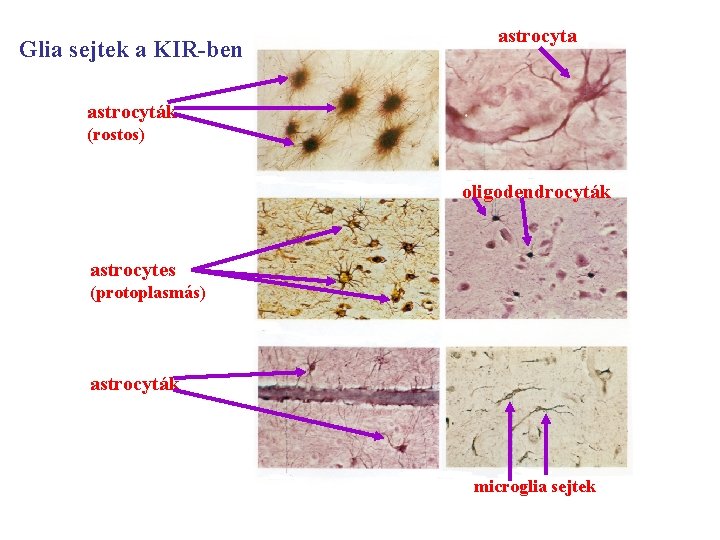

Glia sejtek a KIR-ben astrocyta astrocyták (rostos) oligodendrocyták astrocytes (protoplasmás) astrocyták microglia sejtek